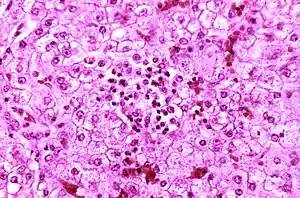

| Appearance of a liver from a child who died of Reye syndrome as seen with a microscope. Hepatocytes are pale-staining due to intracellular fat droplets. | |